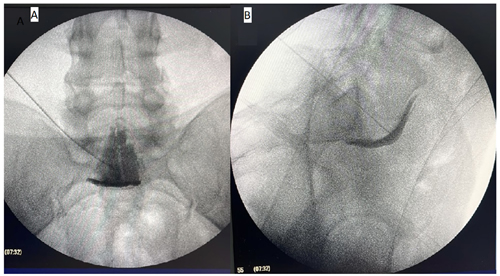

Figura 1